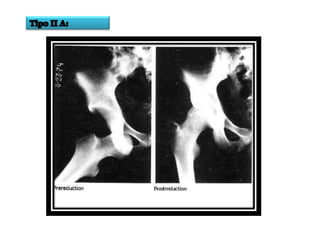

CLASIFICACION DE

THOMPSON Y EPSTEIN

• Tipo I: Luxación posterior pura o con minima fractura

de la ceja acetabular.

• Tipo II: Luxación posterior con una fractura mayor d la

ceja acetabular posterior.

• Tipo III: Luxación posterior y fractura conminución de

la ceja acetabular con o sin fragmento mayor.

• Tipo IV: Luxación posterior con fractura del piso

acetabular.

• Tipo V: Luxación posterior con fractura de la cabeza

femoral.